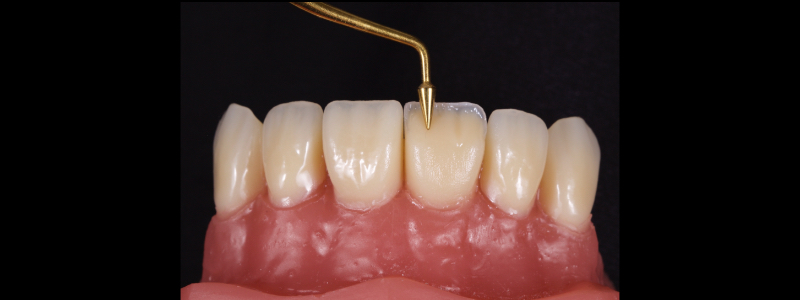

To achieve this, the achromatic enamel mass is first placed on a PVS Putty stent made from a diagnostic wax-up with a flat plastic (see the first article in this series for more detail). The enamel mass is thinned with a flat plastic in combination with a multipurpose condenser, a #3 brush (i.e., GC, Cosmedent, Tokuyama), and some modeling resin (Fig. 7).

A modeling resin is a liquid resin that does not contain HEMA — examples include modeling resin (Bisco), Brush and Sculpt (Cosmedent), and Signum (Kulzer). The unpolymerized resin is then carried in the stent to the tooth and adapted to the palatal margin with a #3 brush (Fig. 8).